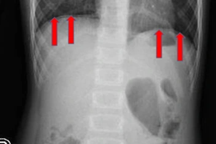

Thạc sĩ, bác sĩ Lê Vũ Trường, chuyên khoa Nội soi cho biết, ngay khi tiếp nhận bệnh nhi, các bác sĩ tại khoa Cấp cứu đã nhanh chóng chỉ định chụp X-quang.

Kết quả chụp chiếu phát hiện đồng xu nằm ngay 1/3 giữa đoạn thực quản. Theo lời kể của người nhà, khoảng 7h sáng, bé trai 6 tuổi nêu trên ngậm đồng xu mệnh giá 200 đồng rồi vô tình nuốt luôn vào bụng. Sau đó, bé có cảm giác nuốt vướng tức vùng thượng vị nên nói với mẹ. Nghe vậy, gia đình nhanh chóng đưa bé vào bệnh viện.

Hình ảnh nội soi cho thấy đồng xu kẹt trong thực quản bệnh nhân (Ảnh: BV).

Qua hội chẩn và tư vấn người nhà, ekip điều trị thống nhất khẩn trương nội soi gắp dị vật cho bé. Sau 15 phút nội soi gây mê, ekip Nội soi đã dùng dụng cụ chuyên dụng lấy đồng xu ra khỏi dạ dày bệnh nhi một cách an toàn, kiểm tra vùng thực quản không thấy trầy xước. Hiện tại, sức khỏe bệnh nhi ổn định và được xuất viện về nhà.